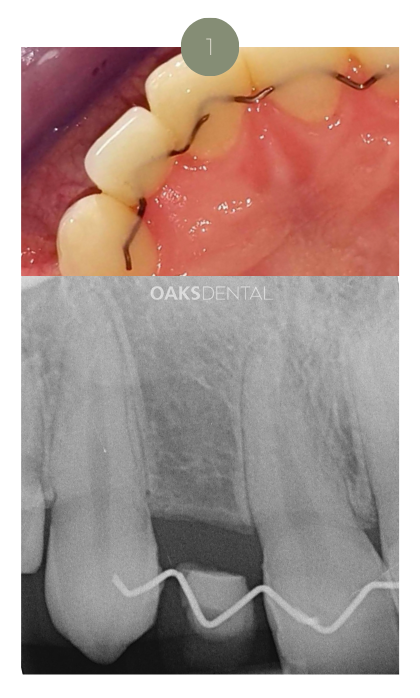

1. Consultation & Digital Scan

Your journey begins with a comprehensive examination, including photographs, X-rays, and 3D scans (CBCT).

These images help assess your bone structure, nerves, and sinuses.

Where appropriate, we design 3D-printed surgical guides to assist in accurate implant placement tailored to your anatomy.